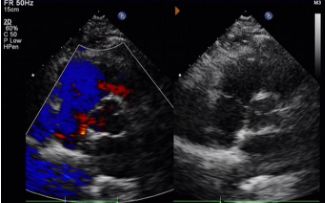

Today, we share a remarkable case highlighting 1-year post-op outcomes of MemoSorb in treating a complex long-tunnel PFO (12mm length, 1.4mm width), with a focus on serial echocardiographic evidence of device degradation and clinical symptom resolution.

Día 1 a 9 meses:

No se observó derivación residual.

Reducción gradual de la ecogenicidad del dispositivo.